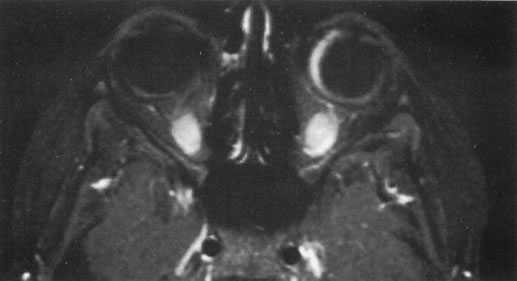

The role of MRI in the evaluation of intraocular masquerade syndromes is unclear. There was initial enthusiasm about the possibility of differentiating atypical uveal melanomas from hemorrhagic-simulating lesions based on the unique paramagnetic properties of melanin.13 In relation to vitreous, a uveal melanoma typically has a bright signal on a T1 image and a dark signal on a T2 image. In contrast, hemorrhagic processes tend to be either bright or dark on a T1 image and bright on a T2 image.14

Unfortunately, there are several problems with MRI for uveal melanoma diagnosis. First, several investigators have shown that unless high field-strength, thin-section scans with surface coils are used, the quality of data obtained is suboptimal.15 Second, even in a state-of-the-art center, we have had a number of cases in which we were unable to differentiate between a uveal melanoma and a simulating lesion on the basis of MRI data. We obtain MRI studies in older patients with opaque media, equivocal ultrasonographic data, and large masses. In some of these cases, the MRI is diagnostic of either a melanoma or an extramacular disciform (hemorrhagic) process. It is also a useful adjunctive study if localized extraocular extension is suspected. In equivocal cases, however, we proceed to using invasive diagnostic techniques, such as fine-needle aspiration biopsy (FNAB) (see Metastatic Tumors).